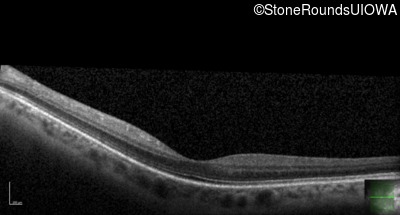

Optical Coherence Tomography - Left - 20/25 -2

Exemplar / OCT Stack